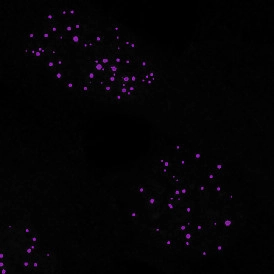

The IF Cellular Microenvironment App allows to determine the cellular phenotype of specific IF-stained cell populations and establishes their spatial relationship between each other and their neighboring cells/cell populations, including those with metastructures (e.g., blood vessels, tumors) in their vicinity. It is especially suited for proximity and infiltration analyses.